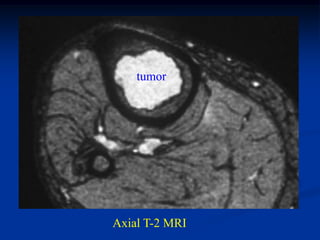

Axial T-2 MRI

Tumor seen thru cortical window